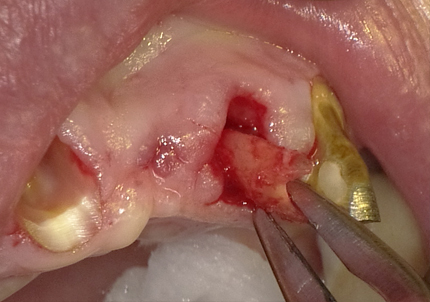

4.左下5番ソケットシールドテクニック

【ソケットシールドテクニックにより保存した歯牙片の内側にインプラントを埋入するCTシミュレーション】

【上記シミュレーションにて作製したガイドを用いたインプラント埋入】

5.インプラント埋入(2021年6月)

※ 初期固定35N/cm確認する